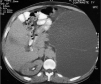

Fig. 2. Tomografía axial computarizada abdominal mostrando una ureterohidronefrosis izquierda gigante que desplaza a los órganos vecinos.